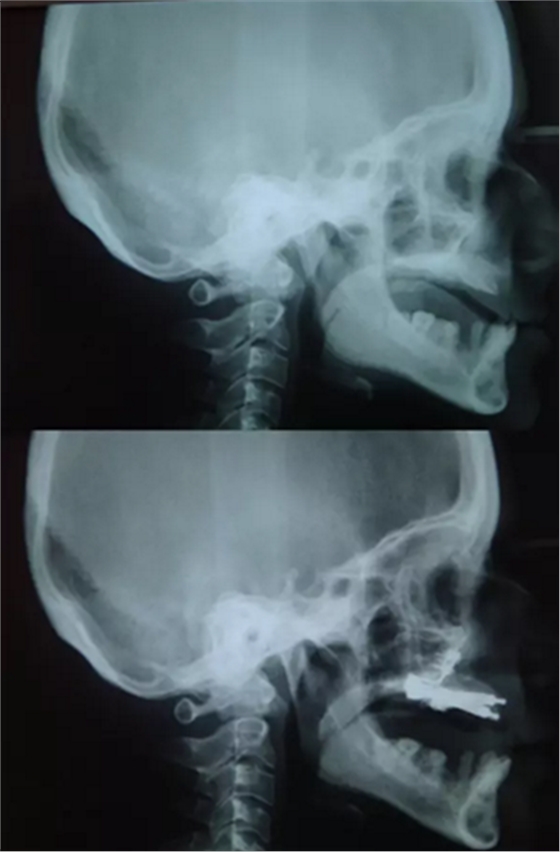

该患者 12 岁时已诊断为釉质发育不全。家族史正常,否认全身系统性疾病。全身系统检查无明显异常,检查双侧颞下颌关节、开口度正常。口内及 X 片检查见上颌缩窄,上颌牙列缺失,安氏三类错牙合,下颌牙牙冠短小,牙根正常。上颌大量牙槽骨因以前手术干预而丧失,后牙区牙槽骨高于前牙区。病变牙齿在之前的治疗中已被拔除。

图 3. 侧位片(术前及牵张前)

该患者的治疗目标是恢复牙颌面的正常功能和美观,包括颌骨的垂直关系及咬合关系。治疗步骤分别是术前诊断,制备引导性义齿,外科手术(Le FortⅠ型截骨牵张成骨),种植体植入及最终的义齿修复。上颌牵张 10 天(每天 0.5 mm×2 次),二期拆除牵张器并行种植体植入,术后出现轻微的感觉异常及开口困难,症状于 2 周后缓解。经头影测量可见 A 点、ANS 点、上唇、鼻尖点分别前移 6 mm、 8 mm、5 mm、2 mm。最后行义齿修复上颌牙列缺失。患者对最终的美观及功能恢复感到满意。